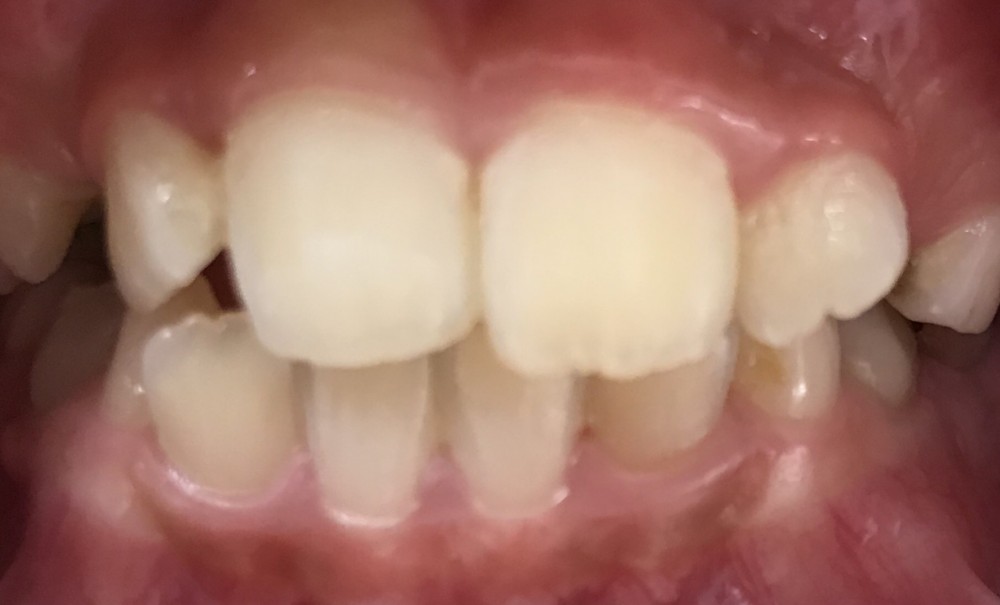

矯正開始から8カ月後の写真です。

今回のケースでは、ここまでで治療費6万円以内、期間は8カ月程度となりました。

この時点で、保護者の方やご本人さまがご満足されたら矯正治療は終了となります。

さらに美しい歯並びにしていく場合には、全顎矯正を検討することになります。